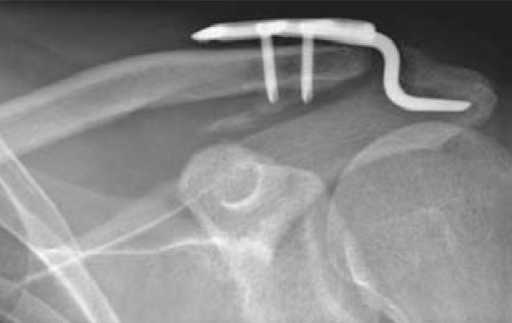

Недавно наткнулся на такого рода "новшество" - пластинка от АО для фиксации разрывов акромеально-ключичных сочленений.

Детальнее по ссылке

фото приложил.

Если с ссылкой не получится - то с главной страницы АО ---> Web Services ---> Innovations ---> Clavicula